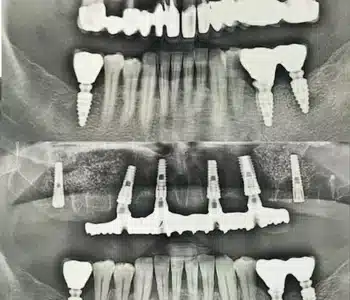

Dr. Seden Aksu is a specialist in modern implantology and surgical dentistry with extensive experience in the management of complex clinical cases. In her practice, she applies comprehensive surgical planning, minimally invasive techniques, and advanced regenerative technologies aimed at restoring both the function of the dentoalveolar system and the aesthetics of the smile. Dr. Aksu has significant experience in performing implant procedures, bone augmentation, and periodontal surgery, including the treatment of patients with severe bone loss. The primary goal of her work is to achieve stable, long-term outcomes in implant rehabilitation and the restoration of oral tissue health.